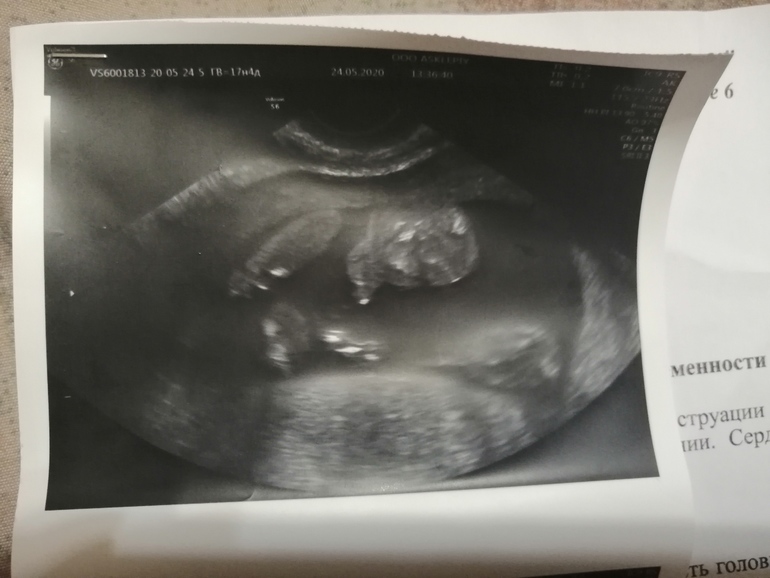

Делал узи по животу, сказал, что девочка.. Затем сделал вагинально, показал причиндалы и сказал, что мальчик.. Я чётко ничего не увидела.. Срок 17 недель был.

Он сделал фотку на память. Ну я думала писька сверху.. Ну а сейчас думаю-неужели это может быть такое огромное, да и между ногами прогал какой получается.. Короче, не пойму.. Кто разбирается, помогите..

На втором скрининге точно покажут. Я на этой фотке вообще ничего не понимаю...